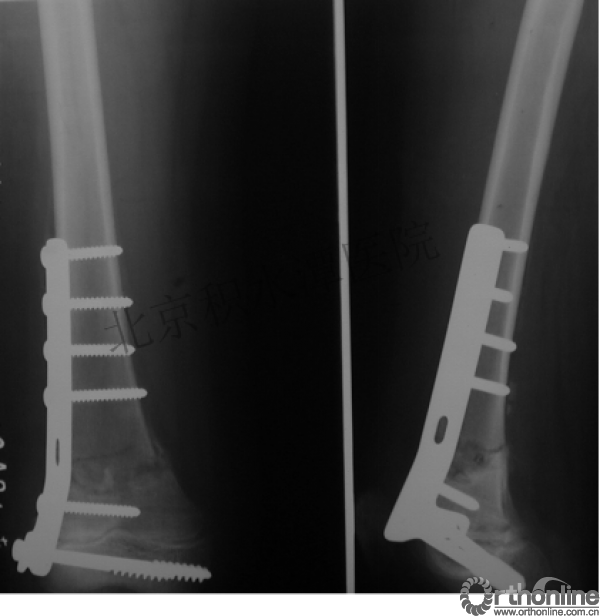

男孩 、5岁,初次骨折于2007年7月。

术后2年→再骨折→再次手术

钢板固定后一年

取板后再骨折→TEN

TEN取出后2个月

闭合复位再固定加尾帽

又过了4年!时间来到2015年

一年以后顺利愈合,实则危机四伏

数月后再骨折!牵引!

髋人字支具

外固定架术后一年

整整11年!是否治疗终结?

病人的付出?医生当反思!

一、思考

1.使用了医生可以使用的所有固定方式

2.似乎哪一次的处理都没有违背原则

3.问题出在哪儿?

4.骨折治疗—手术不是万能的!